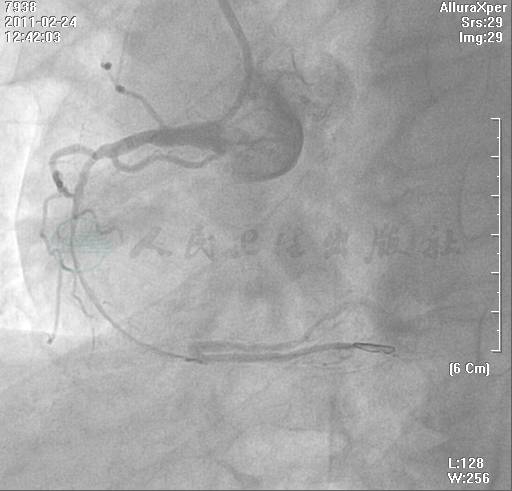

经右股动脉置入6F AL-0.75导引导管至RCA开口;经右桡动脉置入5F TIG造影导管至LCA开口行对侧造影。在微导管辅助下Fielder导丝未通过病变,改用Crosswire NT导丝通过病变,对侧造影证实导丝在真腔内(图4)。分别用Sprint 1.5mm×6mm,Ryujin Plus 1.25mm×15mm和Apex push 1.5mm×8mm球囊,在深插AL导引导管增强支持力基础下反复推送,球囊未通过病变(图5)。决定改用旋磨,将微导管推送至闭塞病变处,撤出Crosswire NT导丝,细心操作交换为旋磨导丝(图6)。用1.25mm旋磨头以11万~13万转/分旋磨,第2次旋磨时旋磨头通过病变,共旋磨20秒×4次(图7~图9)。旋磨结束,撤出旋磨头前后分别造影,RCA残余狭窄80%,管腔光滑、无撕裂、TIMI血流3级(图10、图11)。球囊扩张后植入支架(图12、图13)。

图4 在微导管辅助下Fielder导丝未通过病变,改用Crosswire NT导丝通过病变,对侧造影证实导丝在真腔内